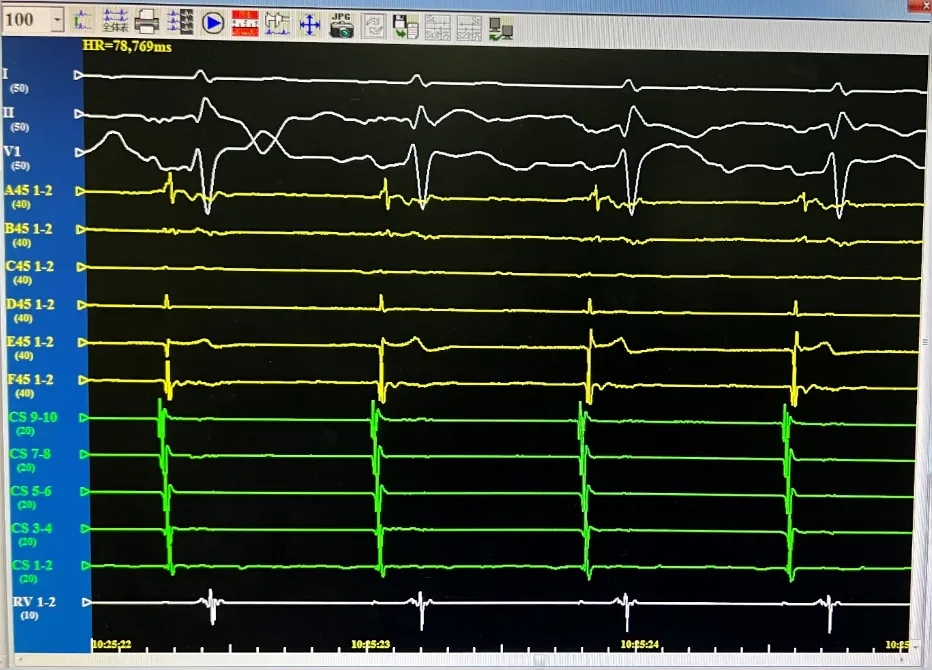

消融导管呈网篮与花瓣形态下放电。

RIPV,消融前后电位。消融后电位即刻消失。

消融后电位验证

消融完成后,分别进行四支肺静脉电位验证。电位无恢复,证明传入阻滞。起搏电极,无法带起心房证明传出阻滞。